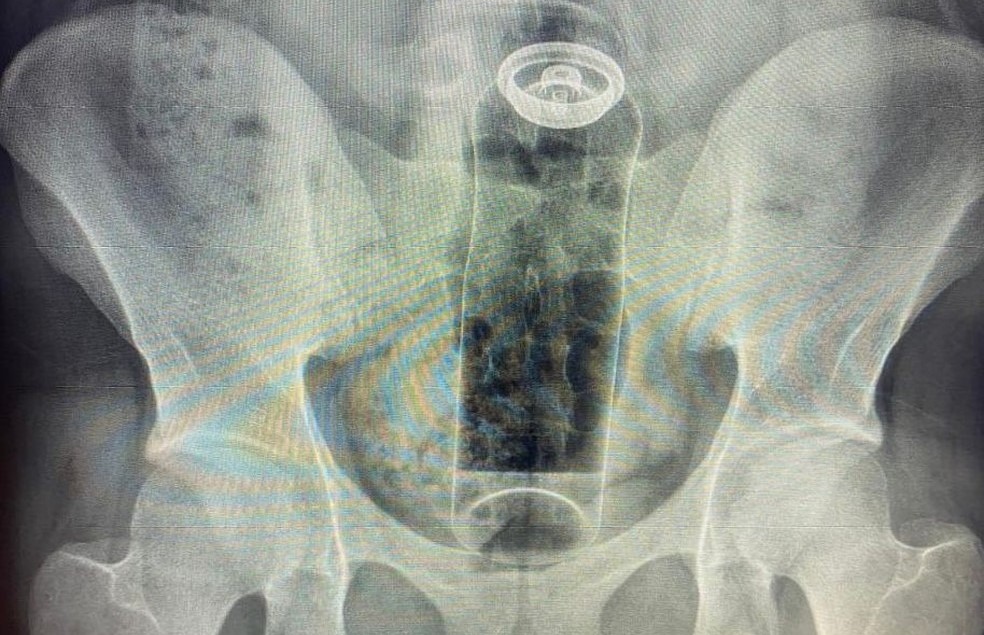

De acordo com o médico Daniel Brosco, cirurgião coloproctologista, o paciente tinha 19 anos e contou que colocou o desodorante no ânus durante uma “brincadeira” sexual. A embalagem, porém, acabou subindo para o reto e não conseguiu ser retirada em casa.

A fantasia não é um problema. O problema é não usar objetos específicos para isso. Imagina se o conteúdo da embalagem vaza ou se o objeto sobe de uma forma que exige cirurgia para retirar? Já tive pacientes que acabaram com infecções graves e morreram.

Leia mais:O médico conta que os casos têm sido cada vez mais comuns e que, nos últimos meses, já atendeu pacientes em que precisou retirar objetos como batata, partes de uma cadeira, garrafa de vidro e plug anal.

🔴 Como isso acontece? O intestino pode “sugar” esses objetos por causa dos movimentos peristálticos — contrações involuntárias responsáveis pelo funcionamento do órgão — ou pelo vácuo criado em áreas como o reto.

Com isso, o objeto pode ficar preso rapidamente. O médico alerta que é preciso buscar atendimento hospitalar o mais rápido possível e não tentar soluções caseiras, como o uso de laxantes. A contração provocada pelo medicamento pode agravar ainda mais a situação.